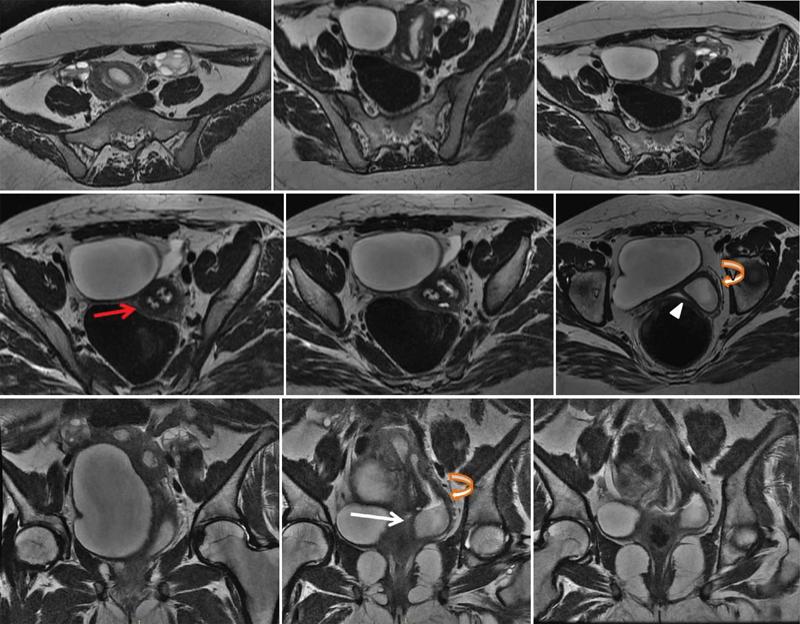

MÜLLERIAN DUCT ANOMALIES Rajani Gorantla Müllerian ducts are a pair of tubular structures that give rise to uterus, cervix, fallopian tubes and upper two-thirds of vagina. Disruption or failure of normal development can result in occurrence of Müllerian duct anomalies (MDAs). These are commonly associated with other congenital anomalies of urinary tract and ovaries due to the close relationship between the development of mesonephric and paramesonephric ducts; few patients also have associated skeletal system anomalies. The prevalence of MDAs in an unselected population was 5.5%; 8% among the infertile women, 12.3% in women with a history of recurrent pregnancy loss and 24.5% in women with miscarriage and infertility. Most of the patients with MDAs are asymptomatic and found incidentally on imaging for any other gynaecological problems, in evaluation of a patient with renal, skeletal or abdominal wall abnormalities. In symptomatic women, complains are related to the type, severity, obstructive anomaly or nonobstructive anomaly. The symptoms can be obstetric or gynaecological related, includes recurrent spontaneous abortions, infertility, preterm labour, intrauterine growth restriction and abnormal foetal lie. Few adolescent girls may present with primary amenorrhoea, hypomenorrhoea, abnormal vaginal bleeding, cyclical pain and mass. Rarely they can present with pelvic inflammatory disease with abnormal vaginal discharge, dyspareunia and urinary tract infections. The female reproductive system develops from a pair of Müllerian or paramesonephric ducts, urogenital sinus and vaginal plate. The ovaries develop separately from the primordial ridge. It is of great importance to understand the normal stages of development, as failure or interruption of any of these stages can lead to a simple to complex spectrum of anomalies. The three stages of Müllerian duct development include: At 6–10 weeks of gestation age, two paired Müllerian ducts and Wolffian ducts formation occurs. When Y chromosome factor (testicular determining factor) is absent, the Wolffian ducts undergo degeneration. The Müllerian ducts further elongate caudally and cross the Wolffian ducts to fuse in the midline. At 10–13 weeks of gestation age, caudal and lateral fusion of the two Müllerian ducts forms primitive uterovaginal canal, which is possessed of solid tissue initially located side by side and further internal canalization leads to the formation of two channels/canals divided by a septum. At this stage, there is reabsorption of the caudal septum and forms single cervical canal and vagina lumen. In around 15–20 weeks of gestation age, complete resorption of the septum takes place in a caudocranial direction from the isthmus to fundus and development of single endometrial cavity results. The fused caudal part of Müllerian ducts gives rise to the uterus, cervix and upper two-thirds of vagina; the unfused cranial part forms the fallopian tubes (Fig. 11.14.1.1). The lower vagina develops from the urogenital sinus, which is separated from the rectum by urorectal septum around 7 weeks of gestation age. The primitive uterovaginal canal embeds into the dorsal wall of urogenital sinus and forms Muller’s tubercle. Around 13 weeks of gestation, two solid masses known as sinovaginal bulbs originate from the upper part of the Muller’s tubercle, further proliferate into the caudal end of the uterovaginal canal to become a solid vaginal plate. Later canalization or degeneration of the central cells of the vaginal plate forms the lower vagina, which is usually completed by 20 weeks’ gestation. The vertical fusion of the upper and lower vagina occurs with resorption of tissue in between and forms single vaginal cavity (Fig. 11.14.1.2). The vaginal lumen is separated from the urogenital sinus by the hymenal membrane. Just before birth, the hymen normally ruptures due to retrogression of the central epithelial cells. However, a thin fold of mucous membrane persists around the vaginal introitus. The ovaries develop separately from migration of primordial germ cells to the genital ridge. Ureteric buds develop separately and concurrently. So renal anomalies are most commonly associated with MDAs with an association of 30%–50%. Various classification systems have been proposed over the past several decades to describe MDAs. Ideally, same classification system needs to be followed by a gynaecologist, surgeon and radiologist for better communication. Buttram and Gibbons classification was suggested in 1979, and it was based upon the level of failure in normal development and segregate the anomalies into groups with similar clinical manifestations, treatment, and prognosis for foetal salvage. According to Buttram and Gibbons, the uterine anomalies were classified into six classes as described in Table 11.14.1.1. The drawback is the lack of classification of vaginal and other anomalies separately. The ASRM (previously the American Fertility Society – AFS) classification system is the most widely accepted classification worldwide over the past years and was introduced in 1988. According to this classification, MDAs are classified into seven classes (class I to class VII) as mentioned in Table 11.14.1.2. However, several limitations have been described by Grimbizis and Campo in 2010 (Fig. 11.14.1.3). The drawbacks of the ASRM classification system are as follows: Hence in 2016, an updated classification of uterine septum, that is ASRM-2016 was proposed and officially approved morphometric criteria are given for distinguishing between septate, normal/arcuate and bicornuate uteri (Table 11.14.1.3). The VCUAM classification was proposed in the year 2005. The main concern is to provide a simple, systematic, clinical classification in addition to providing a precise reflection of the entire malformation. The female genital organs were divided into the following subgroups in accordance with the anatomy: vagina (V), cervix (C), uterus (U) and adnexa (A). Associated malformations were assigned to a subgroup (M) relative to each specific organ. The disadvantage is due to its inherent complexity, and more than 56,700 individual combinations of anomalies are possible. ESHRE and ESGE established a common working group named CONgenital UTerine Anomalies (CONUTA) in order to devise an improved classification system (Table 11.14.1.4). It was published in 2013. Anatomy is the basis for systemic categorization of the MDAs. The subclasses are divided by the different degrees of uterine deformity and their clinical significance (Fig. 11.14.1.4). Cervical and vaginal anomalies are classified into independent supplementary subclasses (Figs. 11.14.1.5–11.14.1.6). For most of the clinicians, it helped as starting point for the development of guidelines for their diagnosis and treatment. The malformations are graded according to severity, U0–U5, C0–C4 and V0–V4, with U5, C4 and V4 being more severe. Class U3 incorporates bicorporeal fusion defects (didelphys and bicornuate) as this was considered as a more functional mode of classification. Arcuate uterus was not included separately, but this is categorized under normal variant into class U1c. Recent studies have demonstrated that the ESHRE/ESGE system provides an effective and comprehensive classification for almost all the currently known MDAs and overcomes the limits of previous classifications. However, there is a relative overdiagnosis of septate uterus with the application of ESHRE–ESGE criteria has been reported and which potentially might lead to unnecessary surgical overtreatment. C0 C1 C2 Normal cervix Septate cervix Double ‘normal’ cervix C3 C4 Unilateral cervical aplasia Cervical aplasia U4 V0 V1 V2 V3 Normal vagina Longitudinal nonobstructing vaginal septum Longitudinal obstructing vaginal septum Transverse vaginal septum and/or imperforate hymen V4 Vaginal aplasia C MDAs’ characterization and classification is of great significance, as the treatment is determined by the type and severity of abnormality. The various imaging modalities available include: HSG was the most recognized imaging modality, earlier to the development of the ultrasonography (USG) and MRI. It is an invasive fluoroscopic-guided procedure for uterine and tubal assessment, and is performed during the midproliferative phase of the cycle, ideally between days 7 and 10 of the cycle when endometrium is thin. Fluoroscopic spot images obtained to evaluate uterine configuration, uterine filling defects and fallopian tube patency. HSG allows evaluation of only the component of the uterine cavity that communicates with the cervix. The anatomic information about myometrium and external fundal contour will not be provided by HSG. The diagnostic criteria used to diagnose MDAs on HSG include: HSG findings of different MDAs are described in Table 11.14.1.5 and Fig. 11.14.1.10. Virtual HSG is a noninvasive technique performed by using a computed tomography (CT) scanner, done 45 s after the contrast material instillation begins. Contraindications are similar to those for HSG and include pregnancy and active pelvic infection. There is no necessity for retraction of the uterus or manipulation of the cervix. The procedure is quick, easy and prophylactic administration of antibiotics is not required. The use of a power injector helps to ensure a steady low pressure of instillation. The procedure is less painful, more comfortable and easily tolerated by patients than conventional HSG. Radiation exposure sometimes requires cervical clamping, which may result in complications such as bleeding and infection. Transabdominal pelvic ultrasound can diagnose uterine anomalies with accuracy rate of 47%. Two-dimensional transvaginal ultrasound (TVUS) has high sensitivity and specificity than transabdominal study and provided some information about external and internal fundal contours. The detection rate is high if the scan is performed in secretory phase due to better visualization of endometrium. Three-dimensional USG shows great accuracy than 2D USG in evaluation of the uterine morphology. The technique of 3D USG varies with different vendors. It displays both the external and internal fundal contours and lower uterine segment by acquisition of single coronal view of uterus (c-view) (Fig. 11.14.1.11). The only disadvantage is that it is transvaginal study and shall not be done in paediatric age group and sexually inactive women. Three-dimensional TVUS has become the first line of screening tool in most of the infertility clinics as it is noninvasive, faster, repeatable, allows storage of volume data and has multiplanar capability for systematic evaluation of the uterine and cervical cavities. The salient features of various Müllerian anomalies on 3D USG are described in Table 11.14.1.6 with images. Three-dimensional ultrasound is combined with sonosalpingography in this technique and provides better delineation of the uterine morphology. It is a less invasive procedure done in proliferative phase with instillation of saline into the uterine cavity and assessment of the uterus will be done. MRI is a universally accepted imaging modality in the documentation of MDAs and accuracy rate of 100% have been reported. MRI provides excellent delineation of both the internal and external uterine anatomies. T2-weighted (T2W) images are the mainstay of pelvic imaging and are performed without fat suppression. T1-weighted (T1W) images are mainly for the haemorrhagic content. The disadvantages of MRI include time-consuming procedure, not cost-effective, large body habitus, pacemakers, recent surgical history and claustrophobia. The current and proposed MRI protocol given by the European Society of Urology (ESUR-MRI protocol) intends a dedicated evaluation of MDAs as mentioned below (Fig. 11.14.1.12): Vaginal anomalies can be accurately diagnosed with the prior administration of the ultrasound gel, to distend vagina (Fig. 11.14.1.13). It will help in better diagnosis of complex vaginal anomalies, like vaginal septations or vaginal duplication. The normal MRI appearance of uterocervical canal and vagina are shown in Fig. 11.14.1.14. Uterine aplasia/hypoplasia/agenesis is class 1 MDA according to ASRM classification and U5 uterine anomaly according to ESHRE classification. It is a formation defect of the paramesonephric ducts with complete or segmental agenesis of uterus and vagina. The incidence rate is around 10%–15% of all MDAs and considered as the most severe form of uterine anomaly. Most of them have complete uterovaginal agenesis with no single completely developed uterine cavity and are associated with Mayer–Rokitansky–Küster–Hauser syndrome (MRKHS). Two types of this syndrome are depicted. The typical form or type A represents the absence or remnants of the uterus, cervix, upper two-thirds of vagina with normal ovaries and fallopian tube (Fig. 11.14.1.15). The atypical form or type B is associated with the abnormalities of the ovaries, fallopian tubes and genitourinary system (Fig. 11.14.1.16). In a few cases (approximately 10%), unilateral or bilateral uterine remnants and with or without endometrial cavity will be seen (Fig. 11.14.1.17). Most of them present with primary amenorrhoea due to complete uterovaginal agenesis and manifest as MRKHS. These patients have normal secondary sexual characteristics due to the preserved normal ovarian function and phenotype. If uterine remnants with functional cavity is present, will present with cyclical pain along with amenorrhoea due to cryptomenorrhoea and haematometra. USG is the first modality for identification of these anomalies, absence of uterus with normal ovaries is diagnostic. But, it is difficult to locate the uterine remnants and cavity due to small acoustic window. MRI is the gold standard and it classifies into uterovaginal agenesis and hypoplasia. If hypoplasia is identified, sagittal and axial sections are taken. These remnants are seen as T2 hypointense tubular structures, located in close relation to ovaries in the adnexa. Once we identify the uterine remnants, it is important to look for the functional endometrial cavity. These will have reduced endometrial and myometrial width. MRI can easily delineate the zonal anatomy due to its high soft tissue contrast resolution. The management of Müllerian agenesis consists of counselling for the patient and her parents. Some patients with MRKHS opt for creation of neovagina for normal sexual life. Various techniques are available. In the presence of a functional Müllerian remnant, regardless of whether it is communicating or not, medical suppression of menses can be initiated and should be followed by laparoscopic removal of the hypoplastic remnant. Unicornuate uterus or hemiuterus is defined as the unilateral uterine development and the contralateral Müllerian duct could be either partially formed or absent. It is a formation defect and the necessity to classify it in a different class than that of uterine agenesis, which is also a formation defect, is due to the existence of a fully developed functional uterine hemicavity. It is considered as class II anomaly according to ASRM classification and class U4 according to ESHRE classification. The frequency rate is around 20% of MDAs. Renal anomalies most often occur in association with unicornuate uterus and usually on the same side of uterine agenesis. Further unicornuate uterus is divided into two subclasses depending on the presence or absence of a functional rudimentary cavity in ESHRE classification: In ASRM classification, unicornuate uterus is divided into four subcategories: Mostly asymptomatic and presence of the noncommunicating uterine remnants will be identified at the time of infertility work up or caesarean section. If a functional cavity is present, the presentation is dysmenorrhoea or haematometra in an adolescent. The common obstetrics-related complications include abnormal foetal lie, intrauterine growth retardation, preterm delivery, placental abnormalities and uterine rupture. Gynaecological complications are ectopic pregnancy and endometriosis due to retrograde menstruation. On imaging, unicornuate uterus is seen as tubular and fusiform or banana-shaped structure at paramedian location, the endometrium is narrow and tapers to the apex with normal myometrial anatomy and reduced uterine volume. The rudimentary cavity or remnants are better depicted on 3D USG (Fig. 11.14.1.18) and MRI. However, MRI is superior to USG due to its high soft tissue resolution. The rudimentary cavity can communicate with main cavity or connected by fibrous band. The nonfunctioning cavity will be seen as T2 hypointense structure with loss of zonal anatomy (Figs 11.14.1.19 and 11.14.1.20), whereas the functioning cavity will show the deformed zonal anatomy (Fig. 11.14.1.21), and its complications like haematometra as T1/T2 hyperintense endometrial collection. Unicornuate uterus without rudimentary cavity does not require any procedure. But in the presence of communicating or noncommunicating rudimentary horn, surgical resection must be considered to prevent complications. Uterine didelphys is a class III MDA based on the ASRM classification and class U3b bicorporeal uterus according to ESHRE classification with an incidence rate of 5% among the uterine anomalies. It is a lateral fusion defect; results from complete failure of the Müllerian duct fusion. Two noncommunicating endometrial cavities with preserved zonal anatomy are seen with separate cervix. According to ESHRE classification, it is defined as external fundal indentation completely dividing the uterine corpus up to the level of external cervical os. It is most commonly associated with longitudinal vaginal septum in around 75% of cases. Some patients may show transverse vaginal septum and these will be obstructive or nonobstructive type. Renal anomalies are also commonly associated with uterine didelphys. Uterine didelphys is usually asymptomatic and diagnosed incidentally on pelvic examination or caesarean section. The uterine didelphys with obstructed vagina (Fig. 11.14.1.22) will present at adolescence as dysmenorrhoea, haematometrocolpos and haematosalpinx. Sometimes retrograde menstrual flow can cause endometriosis and pelvic adhesions. Obstetric-related complications include abortion/foetal growth restriction and poor pregnancy outcome. The uterine didelphys with obstructed hemivagina due to transverse vaginal septum and associated ipsilateral renal agenesis are the manifestations of the syndrome called obstructed hemivagina and ipsilateral renal agenesis anomaly/Herlyn–Werner–Wunderlich (HWW) syndrome (Fig. 11.14.1.23).